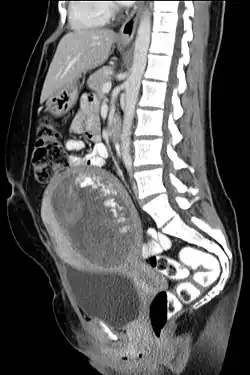

Blasenmole im sagittalen Computertomographiebild